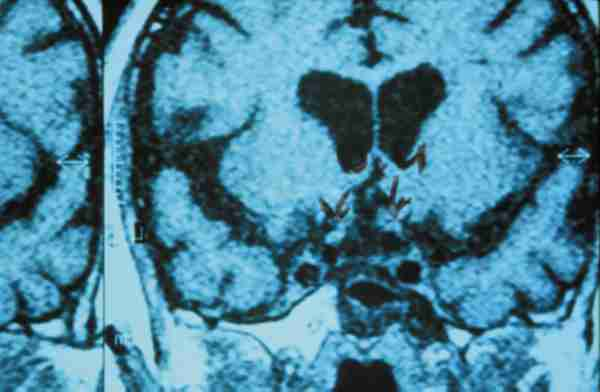

Figura 3

CASO CONTROL.